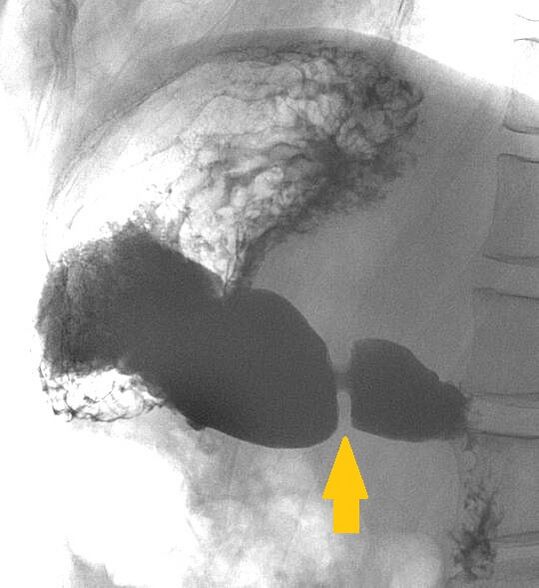

Привра́тник желу́дка (лат. pyloros, греч. πυλωρός — «привратник») — особый сфинктер, отделяющий пилорическую часть желудка от ампулы двенадцатиперстной кишки и выполняющий функцию регулятора поступления кислого желудочного содержимого в двенадцатиперстную кишку по мере её готовности к приёму следующих порций химуса (пищевой кашицы).

В пилорической части различают три отдела: преддверие (vestibulum pylory), пещеру (antrum pyloricum), канал (canalis pyloricus). Преддверие располагается в начальном отделе пилорической части (привратника), затем переходит в пещеру, представляющую суженную часть; канал находится в области сфинктера. Пилорический сфинктер (m. sphincter pylori) имеет форму кольца толщиной 4-5 мм. Слизистая оболочка плотно охватывает пищевой комок за счет сокращения мышц слизистой оболочки. [1]